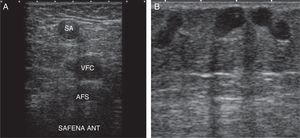

Para demostrar la presencia de reflujo utilizaremos las siguientes maniobras:

Valsalva: aumentando la presión toracoabdominal2,10,11,18 (fig. 8A).

Compresión/relajación distal2,6,10,12: realizar compresión distal hasta que desaparezca el flujo; se considera positivo el reflujo cuando al cesar la compresión se detecta flujo invertido, que se manifiesta como cambio de color e inversión de la curva espectral19,20, en cortes transversales y con Doppler color.

Comenzaremos el estudio a nivel de la unión safenofemoral en modo B (signo de Mickey Mouse) (fig. 8B).